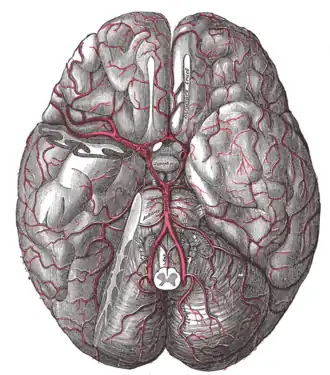

Кровоснабжение гипофиза осуществляется из верхних и нижних гипофизарных артерий, являющихся ответвлениями внутренней сонной артерии. Верхние гипофизарные артерии вступают в воронку гипоталамуса и, проникая в мозг, разветвляются в первичную гемокапиллярную сеть; эти капилляры собираются в портальные вены, которые направляются по ножке в переднюю долю гипофиза, где снова разветвляются на капилляры, образуя вторичную капиллярную сеть. Нижние гипофизарные артерии снабжают кровью преимущественно заднюю долю. Верхние и нижние гипофизарные артерии анастомозируют друг с другом. Венозный отток происходит в пещеристые и межпещеристые синусы твёрдой мозговой оболочки.

Артерии основания мозга -